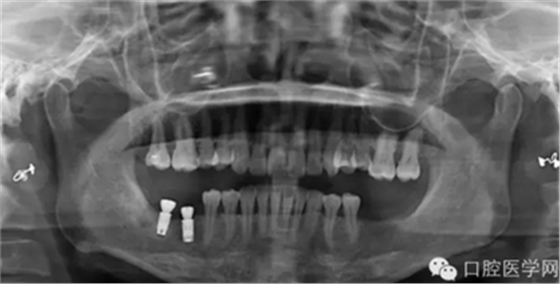

那么今天我给大家展示临床上比较常见的几种品牌的种植体的X光片,网友们可以通过X光片来仔细查看不同种植体之间的区别。因为本人能力有限,不能每一样种植体都拿来尝试使用,所以我目前收集到的种植体的X光片数量有限,但是本人日后还会不断的去寻找不同品牌种植的资料,然后补充道这篇文章中,以供大家参考。

需要特殊声明的是:以下所有的照片中有本人自己的病例术后X光片,也有本人在网络上搜集到的X光片(并非本人的临床病例),所以在此暂不讨论种植体手术植入的角度和设计方案等问题,本文的主要目的是像广大读者展示不同品牌种植体在植入颌骨内拍摄X光片后所显示的形状,用以区别不同品牌的种植体。

第三种是德国Ankylos种植体

第四种,韩国奥齿泰种植体